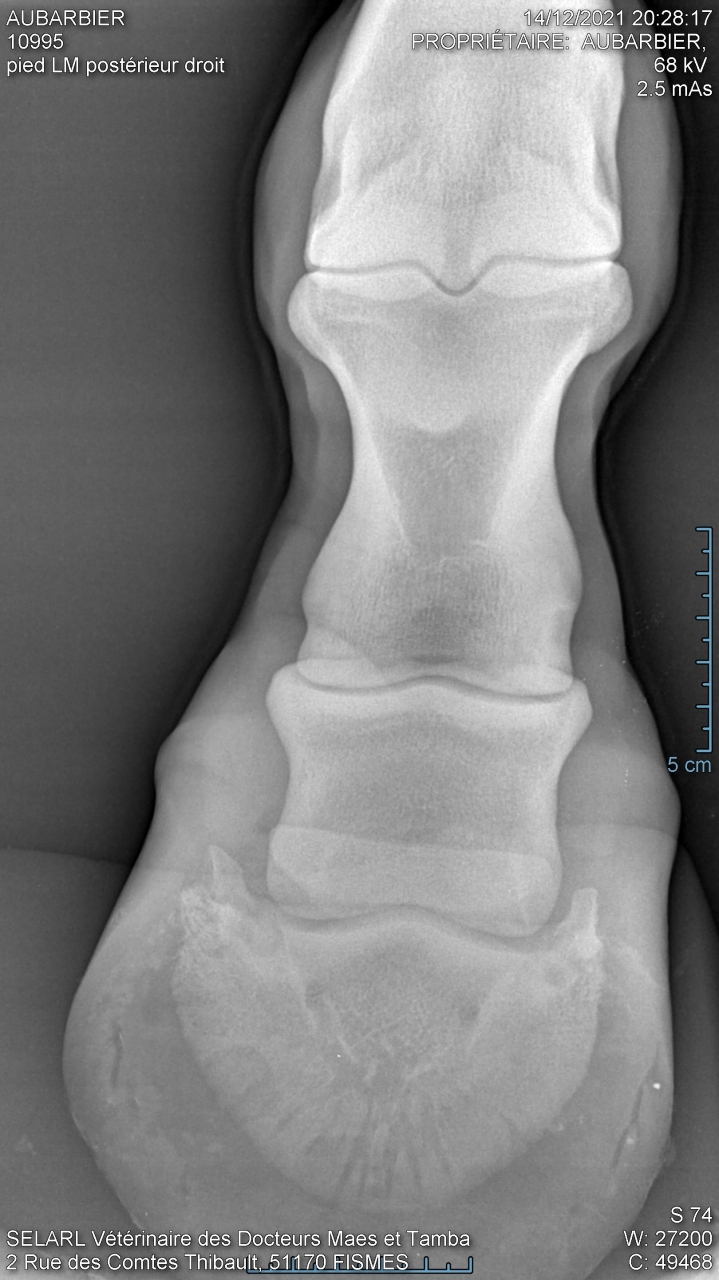

| Dire merci | hello je fais appel à cette commu pour m'aider à comprendre des radios du postérieur de ma jument pour vous situer : je l'ai acheté le 10 novembre de cette année, je l'ai monté 10 fois en tout et à la 10ème séance (13 jours après l'achat) elle s'est mise à ne plus poser le pied par terre (on sautait et elle a boité dès que je suis descendue). Je précise qu'il n'y a eu aucun choc, ni chute. Depuis elle est au box et on a tout essayé chaud, froid, argile, avec fers, sans fers… Tout son postérieur n'est ni gonflé, ni chaud, ni douloureux, et n'a pas mal au test de la pince sur la sol mais impossible de poser son pied ni de lever les autres sinon elle se laisse tomber… La véto a fait des radios que je vais mettre en pièces jointes mais n'a pas rendu de verdict car elle a voulu une relecture par la clinique de Charlevilles Est ce que quelqu'un pourrait m'aider please ? |

| Dire merci | Il n'est pas sur du tout que la pathologie qui fasse boîter votre jument se voit aux radios. Parfois il faut un scanner en plus. Cela peut être tout et n'importe quoi. D'ailleurs la boiterie peut venir d'un autre endroit que l'endroit radiographié. Sans choc/accident évident, vous pouvez être partie pour une batterie d'examens. Avez-vous fait une visite d'achat ? Y avait -il déjà des clichés ? Vous a t-on parlé d'une fragilité particulière ? D'antécédents ? ... |

| Dire merci | Moi je vois un possible chemin d’abcès Qu’a dit la clinique ? |